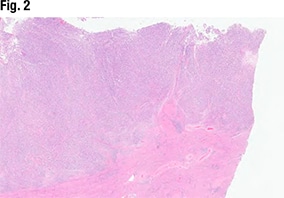

[dropcap]D[/dropcap]r. Sayeed shared the case of a 67-year-old woman who presented with postmenopausal bleeding. The hysterectomy specimen (Fig. 2) revealed a large endometrial tumor, invasive into the myometrium as well (far right). “From this view it looks solid—so not able to see any glandular lumens or glandular morphology, but it does look like a high-grade and solid tumor filling up the endometrium.”